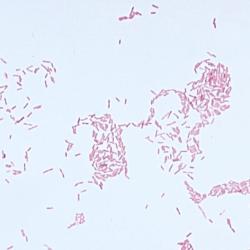

- Gram Stain